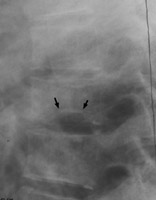

Lateral radiographs of the spine reveals central endplate depression with sparing of the anterior and posterior margins of the endplate. Several current names have been ascribed to these same changes seen in patients with hemoglobinopathy, such as Lincoln Log Sign, or H-shaped vertebra. Although not pathognomonic, these terms are typically reserved for a patient with Sickle-Cell disease.